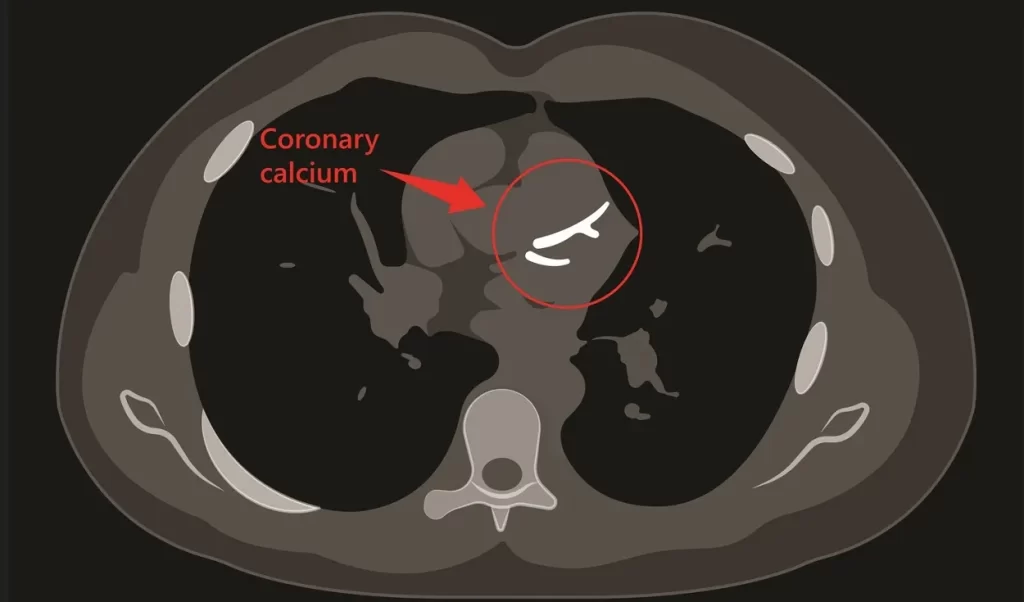

Coronary Calcium Score

A specialized CT scan that measures calcium deposits in your coronary arteries.

How it happens: You’ll lie on a table that moves through a CT scanner. The machine takes multiple images of your heart without using contrast dye. These images reveal calcium deposits in your coronary arteries, which indicate the presence of atherosclerotic plaque. The process takes just minutes and requires no special preparation.

When it’s necessary: This screening test benefits patients with intermediate risk factors for heart disease, helping to guide preventive treatment decisions.